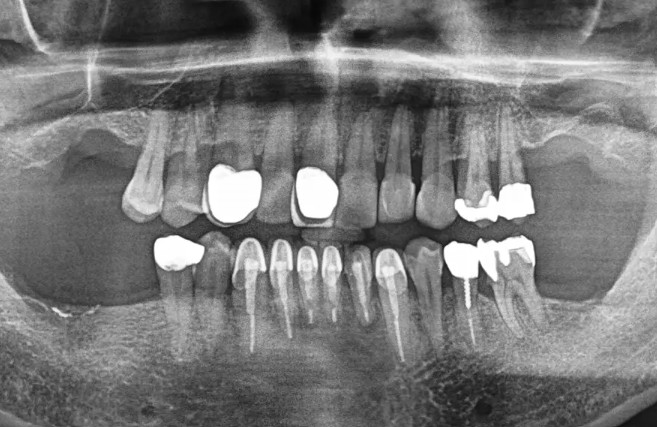

口腔内所見(視診)

左上第1大臼歯(#26)欠損。

隣接歯の金属冠(#25)が摩耗・適合不良で、咬合高径がやや低下。

右側でばかり噛む習慣が形成されており、咀嚼バランスが崩れていました。

歯ぐきの炎症は軽度。歯列全体の清掃状態は概ね良好でした。

画像所見

CTにて、欠損部の骨幅・骨高ともに十分。

上顎洞までの距離にも余裕があり、骨造成(サイナスリフト)は不要と判断。

骨密度も良好で、1本のインプラントで十分な支持が得られる条件が整っていました。